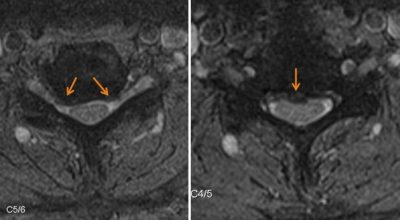

Kernspintomographie (MRT): Degeneration der Bandscheibe C5/C6

Cervikale Myelopathie (grüner Pfeil) durch Bandscheibenvorfall ( roter Pfeil)